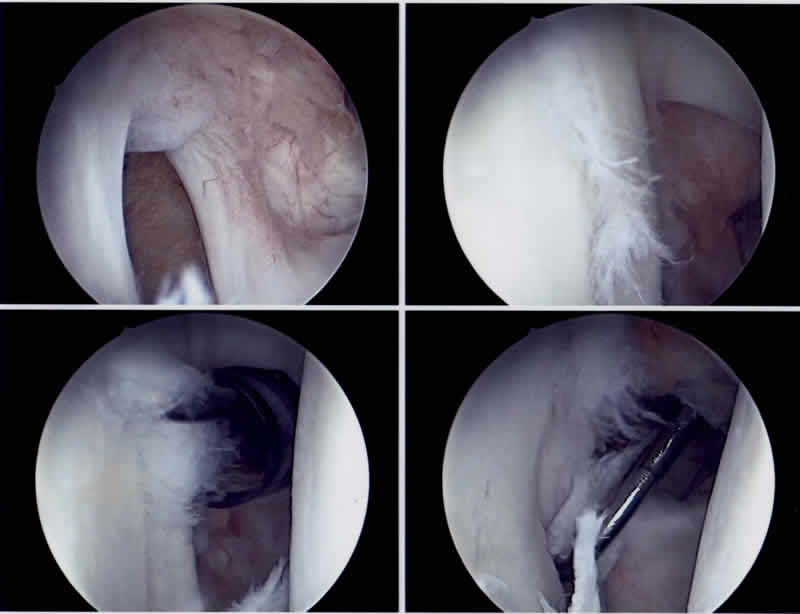

Das Schultergelenk ist das beweglichste Gelenk des Menschen. Dies ist möglich, weil die Schulter nur eine geringe knöcherne Führung mit relativ kleiner Gelenkpfanne hat. Der im Vergleich zur Gelenkpfanne wesentlich grössere Kopf „hängt“ in einer durch knorpelige Pfannenrandanteile (Labrum), Kapselbandstrukturen und Muskelgruppen stabilisierten Gelenkkapsel. Aufgrund dieser hohen Beweglichkeit und der sehr „dynamischen Führung“ ist das Schultergelenk jedoch sehr anfällig für Ausrenkungen (sogenannte Luxationen). Diese treten in den allermeisten Fällen aufgrund eines Unfalles auf: Dabei renkt sich der Oberarmkopf fast immer nach vorne und leicht unter die Gelenkpfanne aus und blockiert dort (sog. traumatische ventrocaudale Schulterluxation). Leider sind Patienten bei denen dieses Ereignis sehr früh auftritt, häufiger und öfter betroffen. So kann es bei jungen Patientinnen und Patienten zu wiederholt auftretenden Luxationsereignissen kommen, dies aufgrund eines durch die Erstluxation gesetzten Schadens am vorderen Gelenkpfannenrand. Durch jede weitere Luxation wird nun die vordere Gelenkkapsel deformiert und ausgeleiert, sodass schliesslich dort eine Schwachstelle entsteht. Wenn mehrfach solche Luxationsereignisse auftreten, sprechen wir von Schulterinstabilität des Oberarmkopfes. Diese ist kaum mehr durch Physiotherapie zu heilen. Nur eine Operation kann die verlorene Schultergelenksstabilität zurückgeben. Ob jedoch eine posttraumatische Instabilität des Oberarmkopfes operativ behandelt werden soll, ist abhängig von der subjektiven Störung, von beruflichen Ansprüchen des Betroffenen und dessen sportlichen Freizeitaktivitäten und muss im Gespräch mit dem behandelnden Orthopädischen Chirurgen entschieden werden.

Ziel der Operation ist es, die normale Schultergelenksfunktion weitestgehend durch die Wiederherstellung der normalen Anatomie zu garantieren, was jedoch infolge des unfallbedingten Gewebeverlustes nicht immer möglich ist. Der optimale Zeitpunkt für eine operative Stabilisierung ist der Zustand nach der traumatischen Erstluxation, da dann der anatomische Schaden vergleichsweise am geringsten ist und die zur Heilung notwendigen Gewebebedingungen ideal sind. Wir empfehlen diese Operation vorallem den jungen Patienten und Patientinnen mit häufigen sportlichen Wurfsportaktivitäten (Volleyball, Handball, Basketball, Beach Volleyball, etc.). Diese Operation wird heute unter Berücksichtigung verschiedener Faktoren, fast immer arthroskopisch, das heisst minmal invasiv durchgeführt.